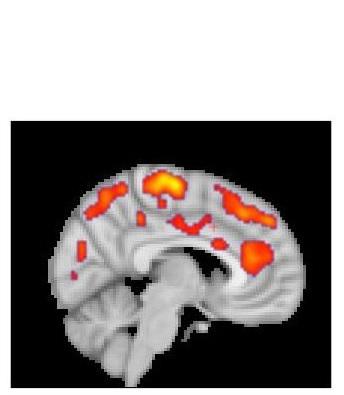

La fibromyalgie se caractérise par des symptômes tels que des douleurs chroniques généralisées, des problèmes de sommeil, la fatigue, des troubles de la pensée et de la mémoire. De précédentes recherches de l’équipe du Karolinska, déjà dirigées par le Dr Eva Kosek, auteur principal de la nouvelle étude avaient suggéré le rôle possible de la neuro-inflammation en particulier de taux élevés de protéines inflammatoires dans le liquide céphalorachidien, chez les patients atteints de fibromyalgie. La nouvelle étude met en évidence, via IRM / TEP, des zones du cerveau dans lesquelles les patients atteints de fibromyalgie présentent une activation gliale plus importante que les témoins (voir visuel 2).

Une suractivation gliale répandue dans le cerveau : les résultats montrent que l'activation gliale dans plusieurs zones du cerveau des patients fibromyalgique est significativement plus importante que chez les témoins. Ces zones d’activation, largement répandues dans le cerveau correspondent aux symptômes plus complexes de la fibromyalgie. Ce type d’activation observé dans le gyrus cingulaire, une zone impliquée dans le traitement des émotions semble correspondre au syndrome de fatigue chronique – selon les niveaux de fatigue signalés par les patients. Enfin, les microglies semblent les principaux responsables de l'augmentation de la neuro-inflammation chez les patients atteints de fibromyalgie.